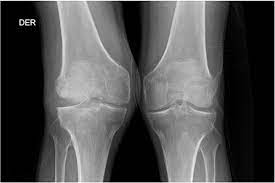

El reumatismo palindrómico es una enfermedad de causa desconocida, caracterizada por ataques recurrentes y frecuentes de inflamación articular aguda que ocurren a intervalos irregulares. Estos episodios se manifiestan con dolor…